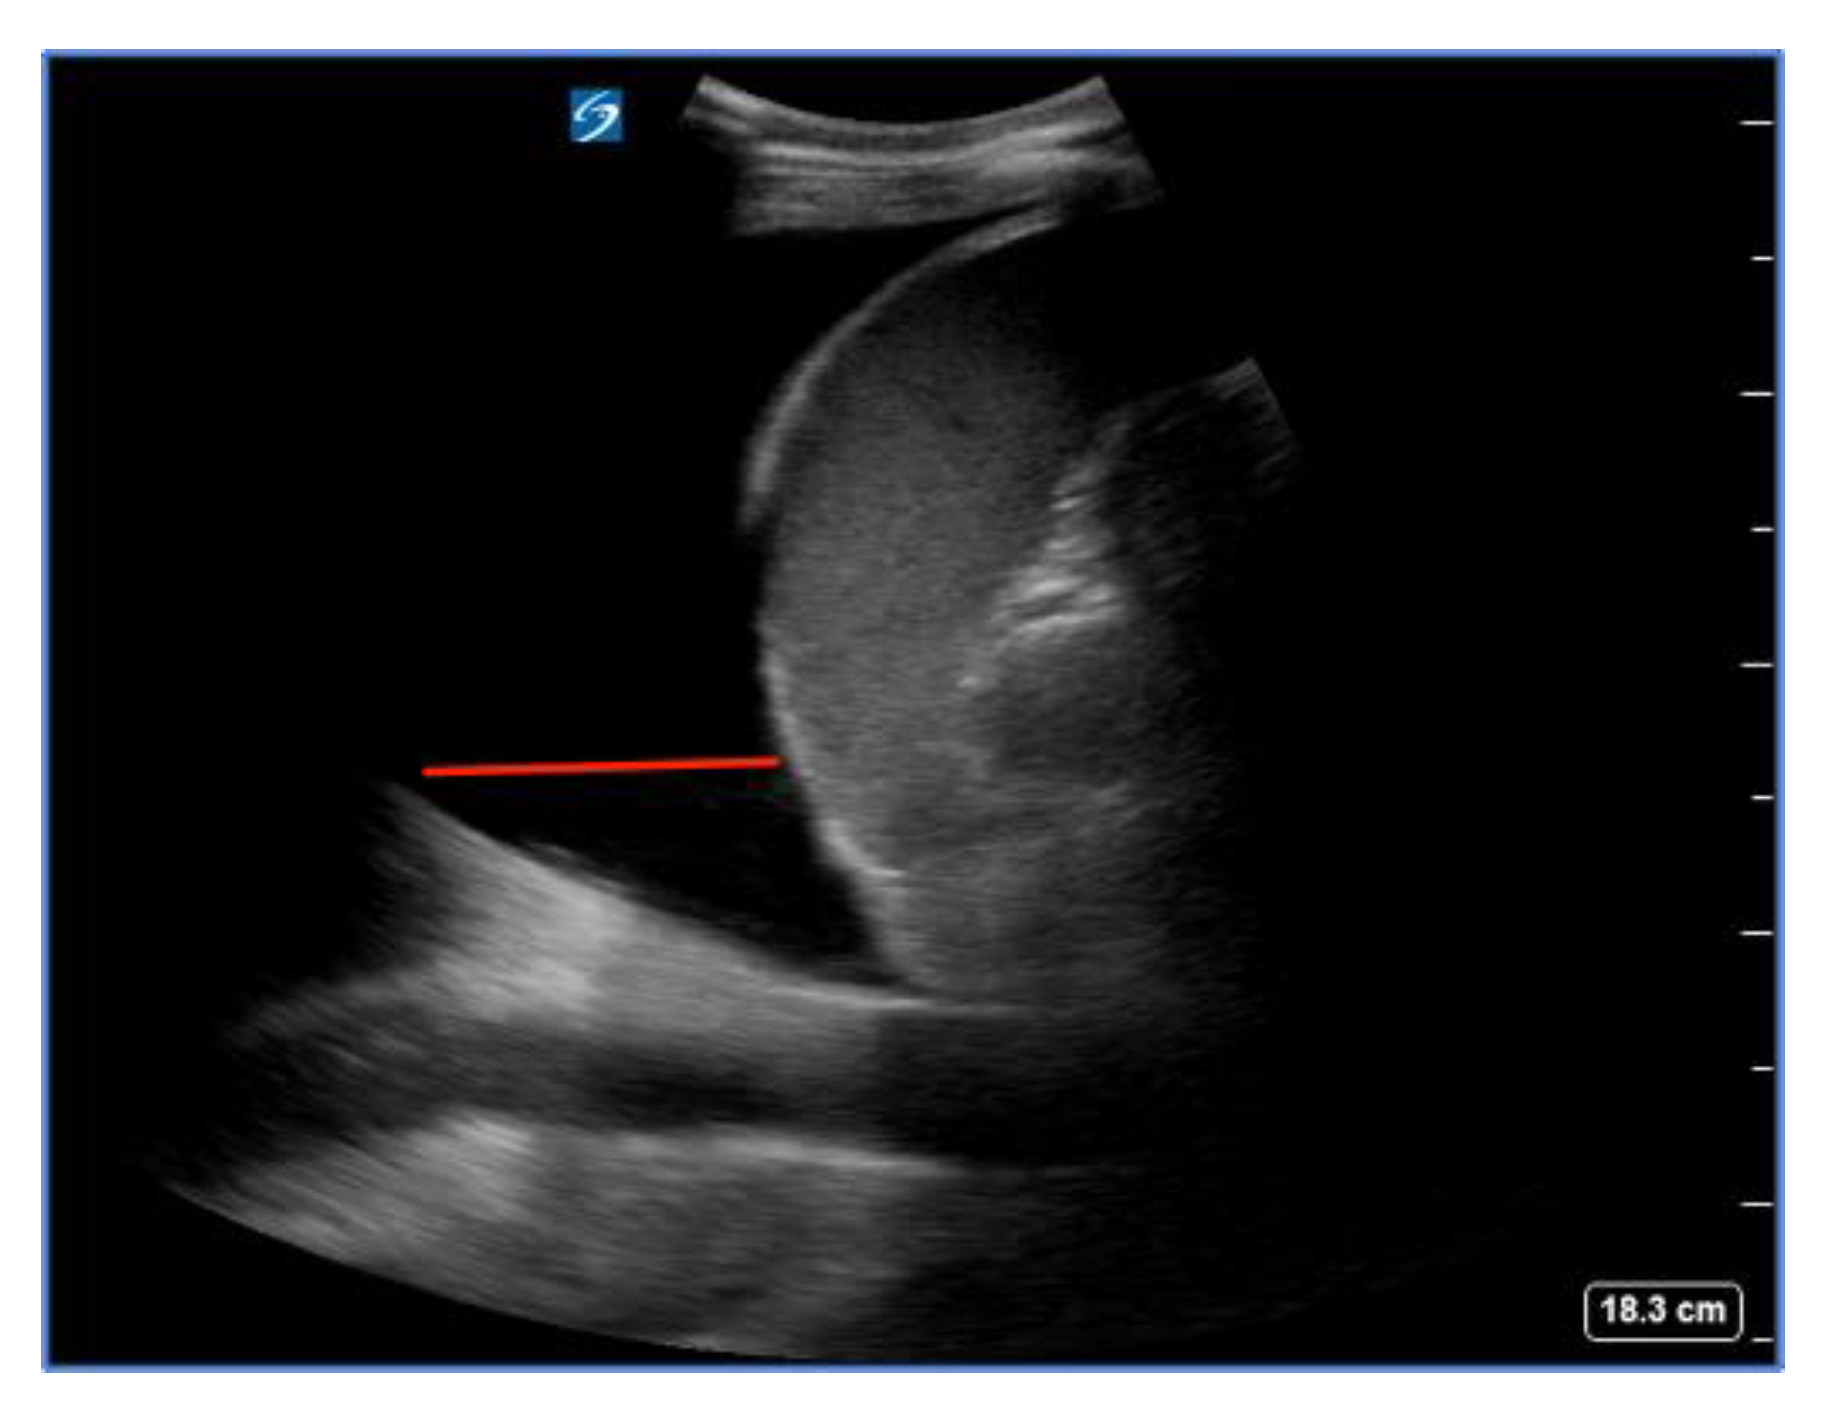

The inferior vena cava (IVC) acts as a vital blood reservoir, holding 85% of the total plasma volume within the venous circulation. Adjustments of circulating volume lead to variations in the caliber of the IVC. Indeed, the finding of a “flat vena cava” (e.g., an IVC with an anteroposterior diameter of less than 9 mm) at multiple levels is associated with significant hypovolemia (Figure 6) [32]. The IVC is usually visualized from a subcostal view via a longitudinal scan, including the veno–atrial junction and the right atrium with the inner walls clearly visible. In case of a suboptimal or unavailable subcostal window, a coronal transhepatic scan along the posterior right axillary line may be an effective alternative. Most authors suggest that measurements should be taken within 1.5 cm from the IVC-to-right atrial junction [33]. However, it is essential to consider that the interpretation of IVC measurements in the context of hypovolemia is not always straightforward. Venous congestion during CPR can limit the significance of the IVC assessment. Other factors such as intrathoracic pressure changes due to mechanical ventilation, individual patient characteristics, and concurrent medical conditions can influence IVC size and collapsibility [34,35].

Figure 6.

Normal (a) vs. collapsed IVC (b) indicated by the red lines, suggesting hypovolemia.